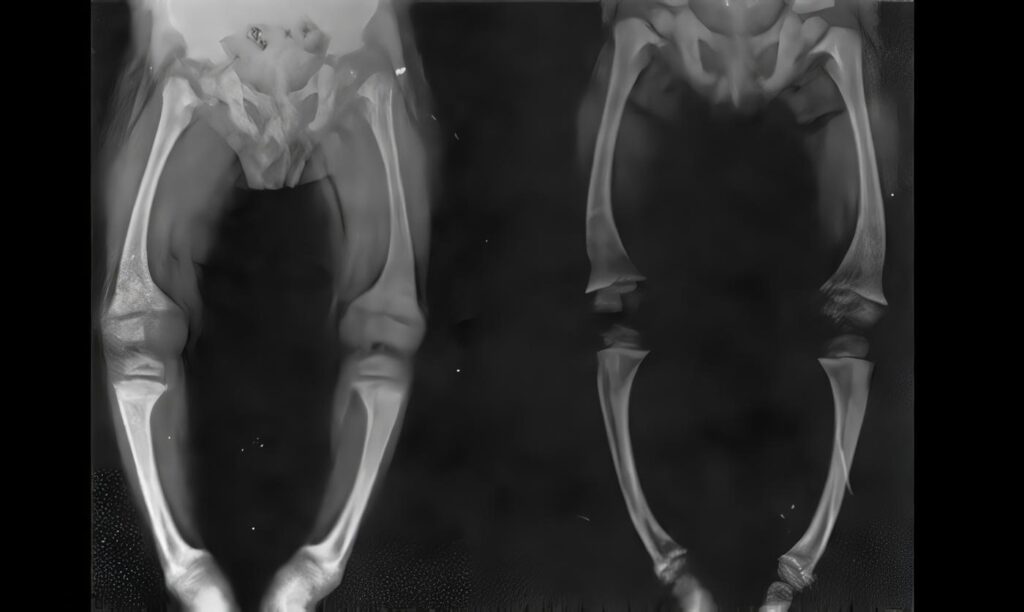

Radioterapia y Crecimiento

Sao Paulo. La radioterapia para niños leucémicos es responsable de secuelas tardías, particularmente en lo relacionado con el crecimiento y...